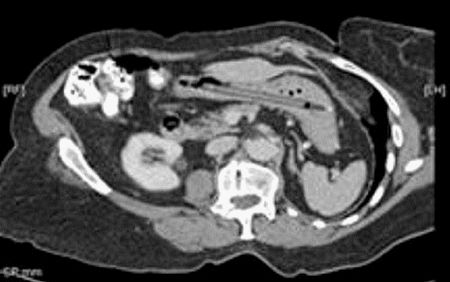

Ảnh chụp cây viết nằm trong bụng của bệnh nhân.

Sau khi chụp cắt lớp, các bác sĩ phát hiện ra một vật thể lạ trong bụng người phụ nữ này, có hình dáng giống với với một cây bút.

Các bác sĩ sau đó đã tiến hành phẫu thuật và lấy ra cây viết dạ ra khỏi bụng bệnh nhân này. Một điều đáng ngạc nhiên là cây bút vẫn có thể viết được hoàn toàn viết được bình thường, sau 25 năm nằm trong bụng của bệnh nhân.